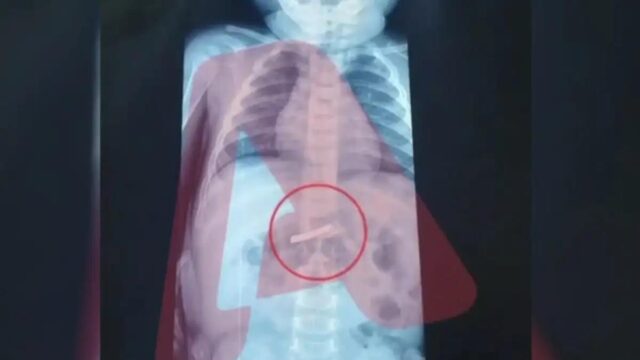

Σοβαρό περιστατικό συνέβη στο Νοσοκομείο “Παίδων” όταν ένα τρίχρονο αγοράκι μεταφέρθηκε εσπευσμένα καθώς είχε καταπιεί ξυραφάκι.

Σύμφωνα με τις πρώτες πληροφορίες, το παιδάκι μεταφέρθηκε άμεσα για χειρουργική αντιμετώπιση, καθώς η κατάσταση κρίθηκε επείγουσα. Πριν από την επέμβαση, οι γιατροί προχώρησαν στις απαραίτητες εξετάσεις και συγκεκριμένα σε ακτινογραφία, η οποία επιβεβαίωσε τις ανησυχίες των γονιών: στο στομάχι του παιδιού υπήρχε πράγματι ένα ξυραφάκι, όπως εκείνοι είχαν ήδη ενημερώσει το ιατρικό προσωπικό.

Η ακριβής θέση του αντικειμένου εντοπίστηκε με σαφήνεια, γεγονός που επέτρεψε στους χειρουργούς να σχεδιάσουν με προσοχή την επέμβαση. Με γνώμονα την ασφάλεια του παιδιού και τη μέγιστη δυνατή ακρίβεια, προχώρησαν στην αφαίρεση του ξυραφιού, αποφεύγοντας επιπλοκές.

Η χειρουργική επέμβαση ολοκληρώθηκε με επιτυχία και, σύμφωνα με τις ίδιες πληροφορίες, το μικρό παιδί βρίσκεται πλέον σε στάδιο ανάρρωσης, με την κατάστασή του να εξελίσσεται ομαλά.